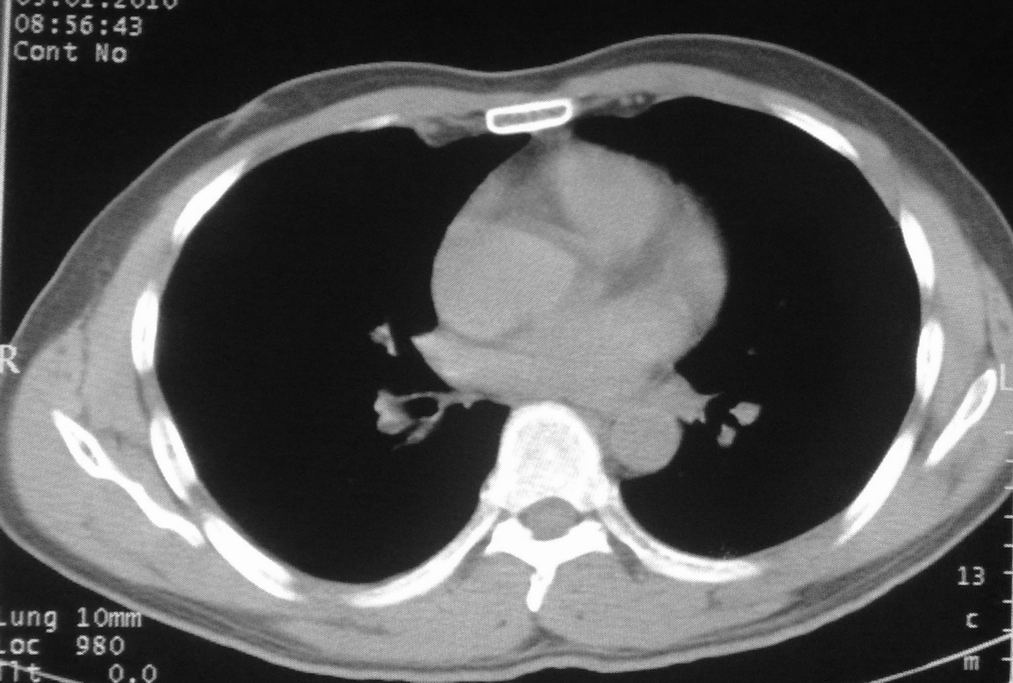

男,51岁,左胸前区不适数天。

薄壁空洞,边缘毛刺,胸膜凹陷,考虑肺癌,结核不排除。

考虑左肺下叶感染性病变。

考虑左肺下叶感染性病变。支持!建议查痰、hrct。

做个hrct,图像再清晰点。